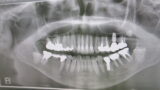

今日は昭和大学旗の台校舎で鈴木教授の歯内療法の講習会に参加して来ました。